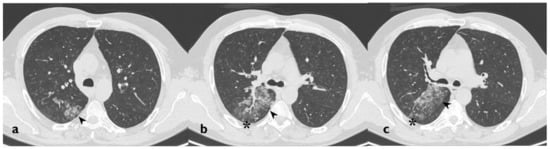

| HRCT Pattern | Associated Drugs |

|---|---|

| Fibrotic pattern | Nitrofurantoin (chronic toxicity), methotrexate, sulfalazina, rituximab, tocilizumab, bleomycin, busulfan, cyclophosphamide (chronic toxicity), amiodarone (form with fibrous course), tocainide, cocaine |

| Organizing pneumonia | Nitrofurantoin (chronic toxicity), methotrexate |

| Mosaic pattern | Nitrofurantoin (acute toxicity), methotrexate, sulfalazina |

| Isolated ground glass | Rituximab, tocilizumab, cyclophosphamide (acute reaction), amiodarone (initial stage), cocaine |

| Alveolar hemorrhage | Penicillamine, rituximab, cocaine |

| Pulmonary edema | Acetyl-salicylic acid, mitomycin |

| Pleural effusion | Sulfonamides, methotrexate |